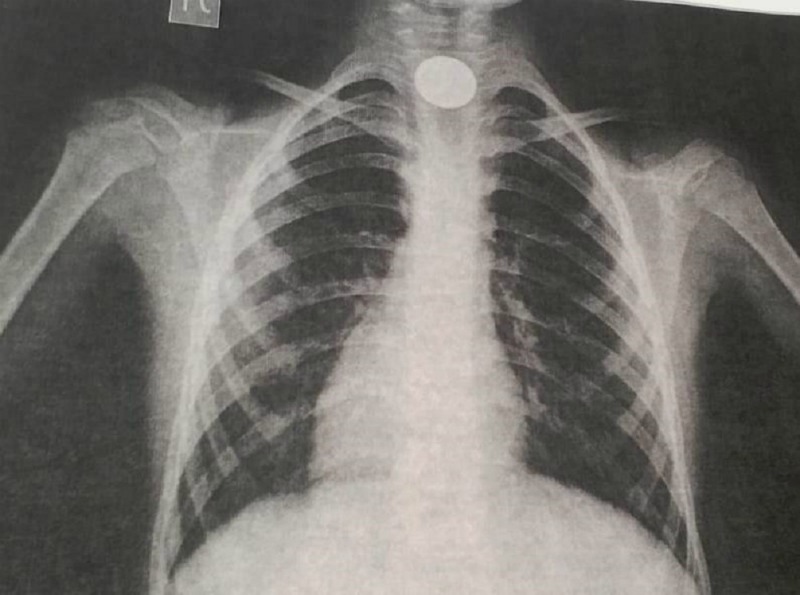

Белгілі болғандай, ойнап отырған 9 жастағы бала байқамай тиынды жұтып қойған. Бір сағаттан соң оның тыныс алуы қиындап, жағдайы нашарлаған. Бұдан соң, ол облыстық көпбейінді балалар ауруханасына жеткізілген. Өкпе жасушаларын түсірген рентгенография қорытындысы өңештің жоғарғы жағында бөгде заттың тұрғандығын анықтаған.